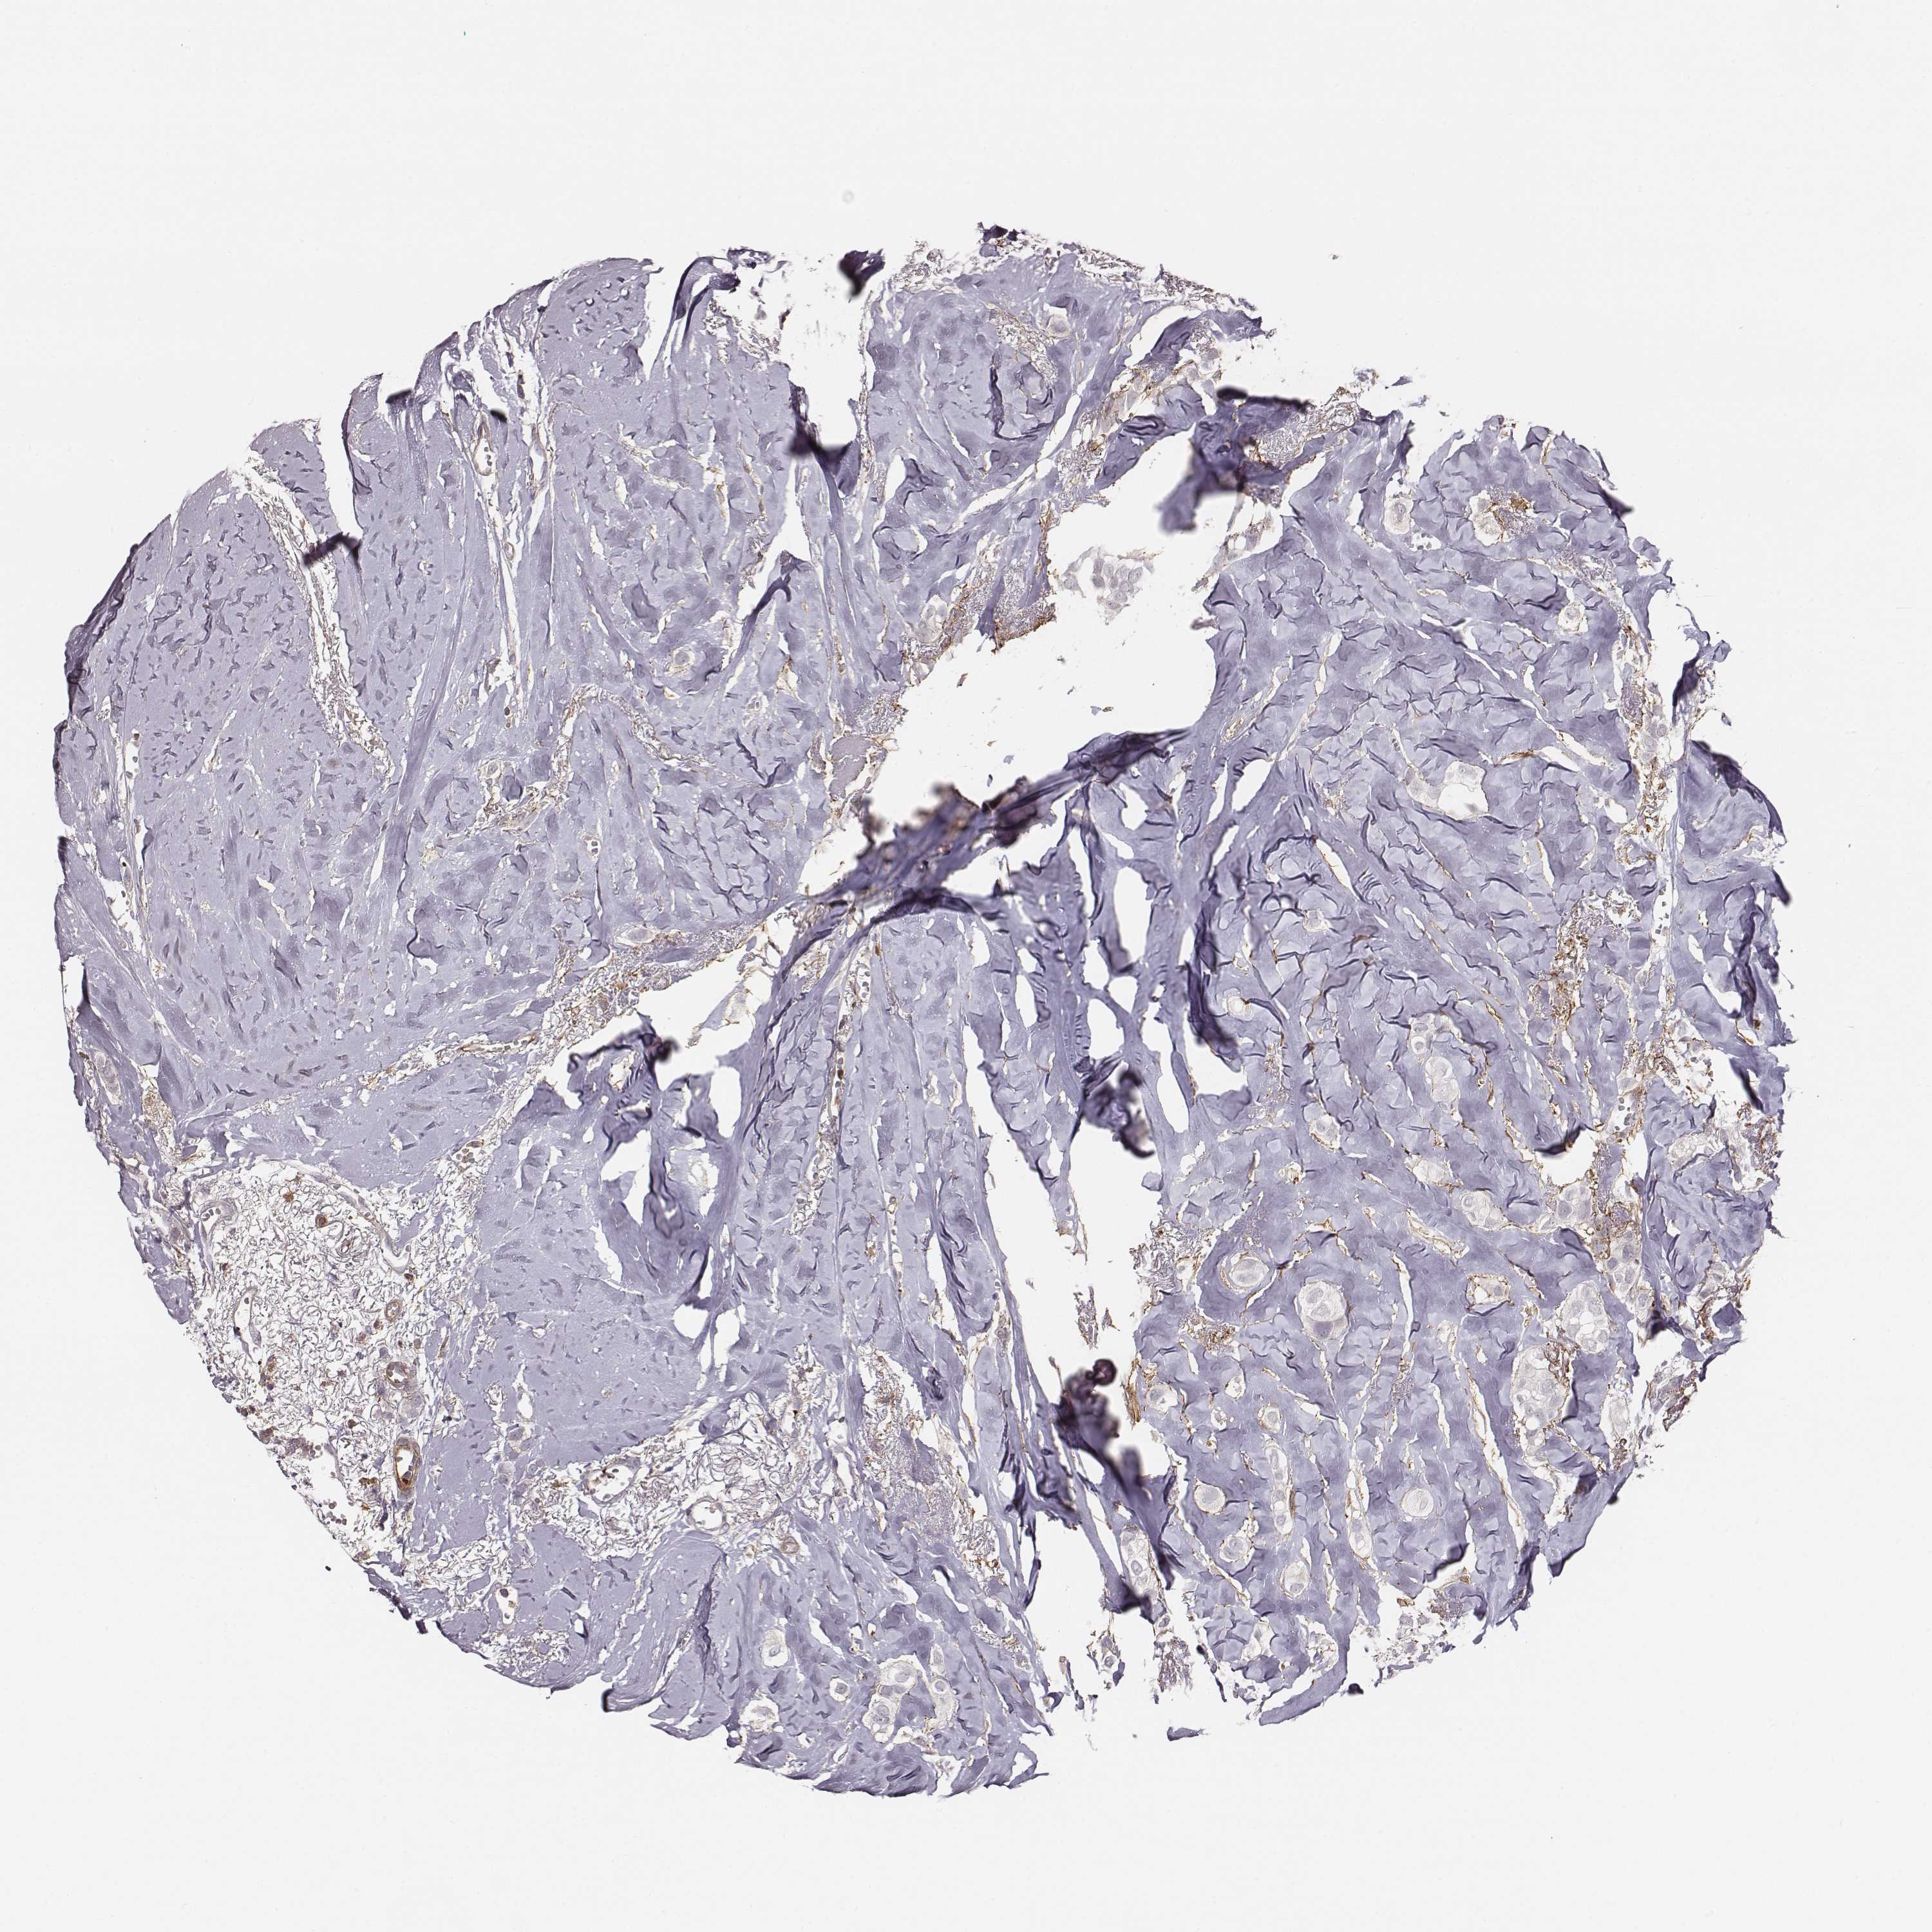

CANCER BREAST CANCER Show tissue menu

BRCA TCGA BRCA VALIDATION PROTEIN EXPRESSION